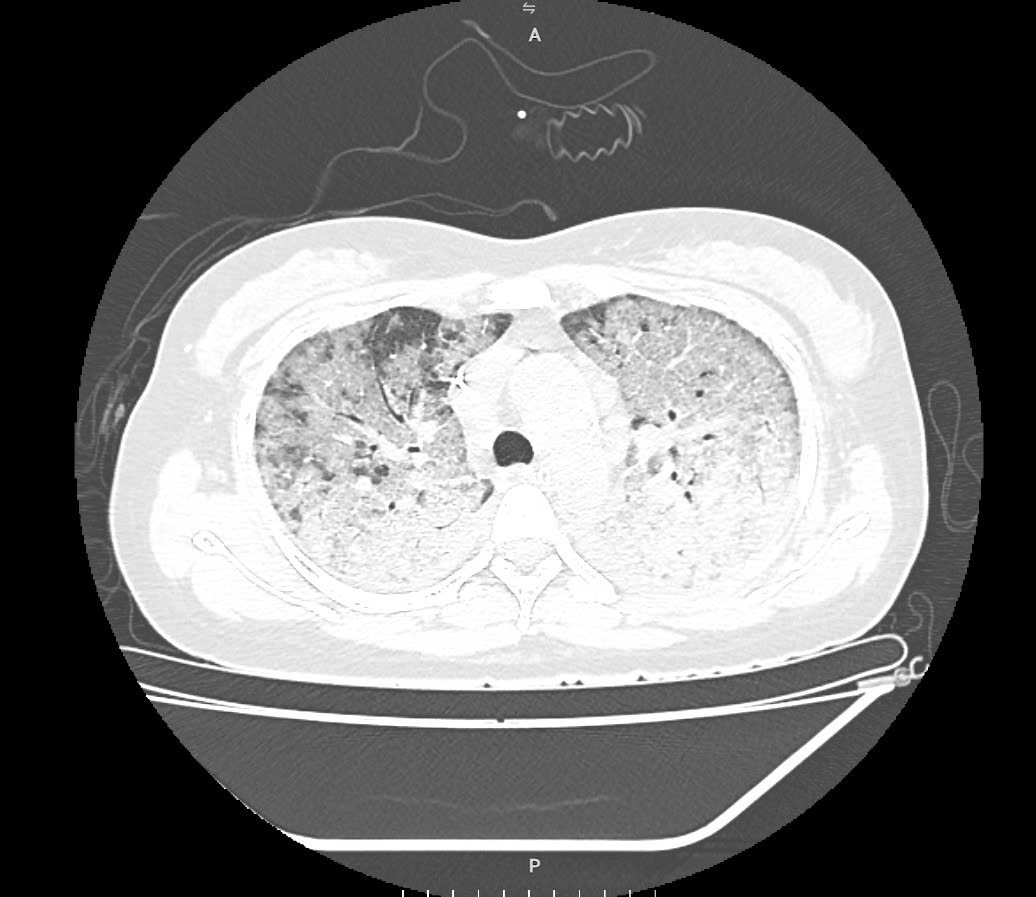

Tuy nhiên, diễn biến cúm xấu lên nhanh đến mức có thời điểm dù cài 100% oxy, SpO₂ vẫn chỉ đạt 80-85%. Hình ảnh phim phổi cho thấy tổn thương lan tỏa kín hai bên phổi, hình ảnh kính mờ điển hình của cúm tiến triển, nhanh chóng chuyển sang hội chứng suy hô hấp cấp (ARDS) - biến chứng nặng thường gặp ở nhóm bệnh nhân suy giảm miễn dịch.

Hình ảnh phim phổi cho thấy tổn thương lan tỏa kín hai bên phổi, hình ảnh kính mờ điển hình của cúm tiến triển. Ảnh: BVCC.